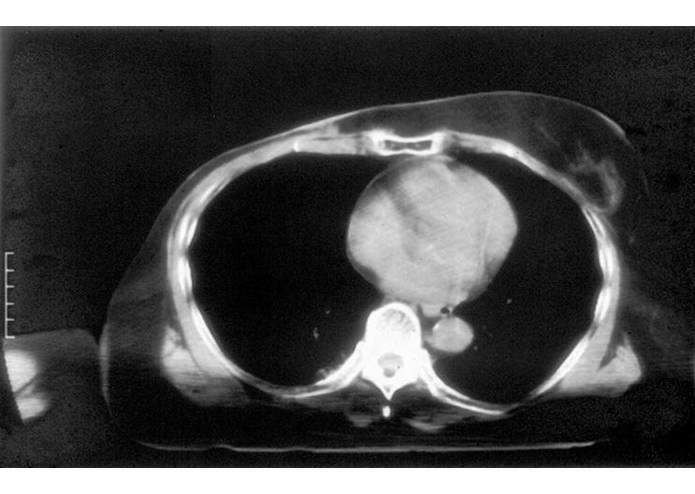

Accomplishments that I'm proud of The concept of a wearable multi-antenna array that includes non-invasive thermometry with a thin and flexible fiberoptic sensor array fitting the inner surface of the vest, and subsurface monitoring of tumor temperature with microwave radiometry. These concepts have attracted previous NIH funding sufficient to complete theoretical optimization of the applicators and integrate the heating array with a comfortable elastic fabric covered waterbolus compartment that effectively cools the skin and avoids potentially painful hot spots. Several different size prototype microwave vest applicators have been assembled and tested in a 14 patient clinical trial. The published results demonstrate significantly improved extent of heating over the best alternative heat applicator, along with improved comfort for the patient.

What I learned The microwave vest effectively heats large areas of chest wall, while being more comfortable for the patient than alternative box shaped applicators that do not conform well to the tissue surface. All aspects of the required heating system are technically feasible and just need a commercial enterprise to build and obtain regulatory approval to use the new device. The device will be particularly suitable for drug companies with temperature sensitive drug carriers and for thermal oncology treatment centers that need uniform heat application to sensitize recurrent tumor treatments to radiation and/or chemotherapy.